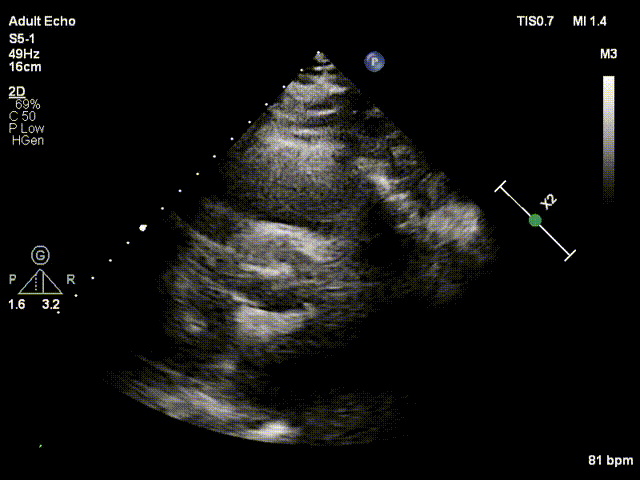

三、超声评估

超声心动图显示患者重度主动脉瓣狭窄伴中度关闭不全,Vmax 5m/s, PG mean 59mmHg,PG max 102mmHg;室间隔16mm,左室后壁13mm;LVDd=40mm,LVDs=26mm;LVEF=62%。

术中超声评价:跨瓣流速1.6m/s,平均跨瓣压差5mmHg,可见少量瓣周漏。